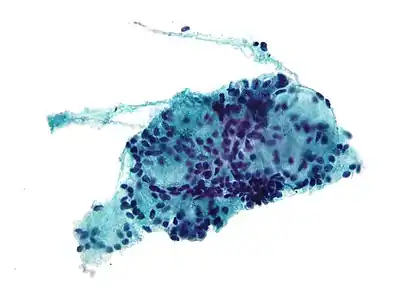

Micrograph of a needle aspiration biopsy specimen of a salivary gland showing adenoid cystic carcinoma. Pap stain. | |